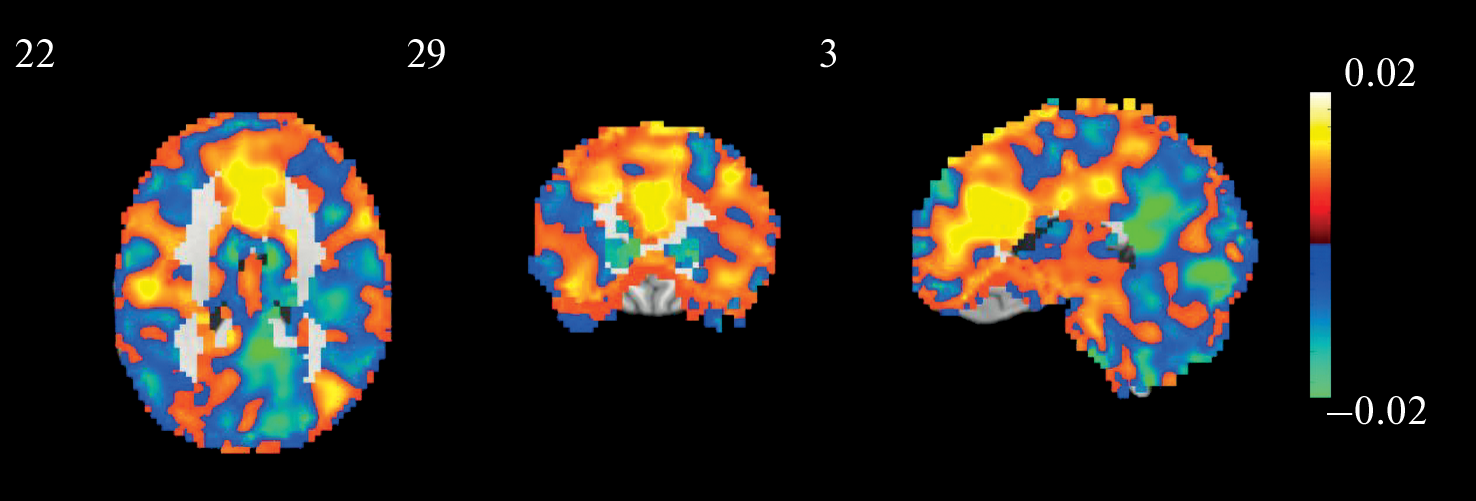

The study of brain activity in the processing of self-referential information, as compared to the processing of information related to other people, is based on the application of mass-univariate analysis, based on the assumption that activity in one region is independent of activity in other regions. Recently, there has been a growing interest in neuroimaging to investigate spatially distributed information using multivariate approaches such as multivoxel pattern analysis (MVPA). In this paper, we used MVPA to analyze fMRI data recorded during self-evaluation and evaluation of other people of varying proximity. In all pairwise classifications tested, the number of correct identifications was significantly higher than the level of random matches. Predictively significant structures were widely distributed over different brain regions and included areas of the visual, lateral prefrontal, and many other cortical areas in addition to the cortical midline structures that contributed the most. In the self-other classification, ventral areas of the medial prefrontal and cingulate cortex were the most informative for the self condition, whereas parietal and occipital medial areas were the most informative for the other condition. The combination of brain structures, which included the anterior cingulate cortex and both amygdalae, revealed by principal component analysis, correlated positively with the psychometric scale of sensitivity to reward, and negatively with neuroticism scales. Overall, the results show the fruitfulness of using machine learning methods to analyze data from such kinds of experiments.